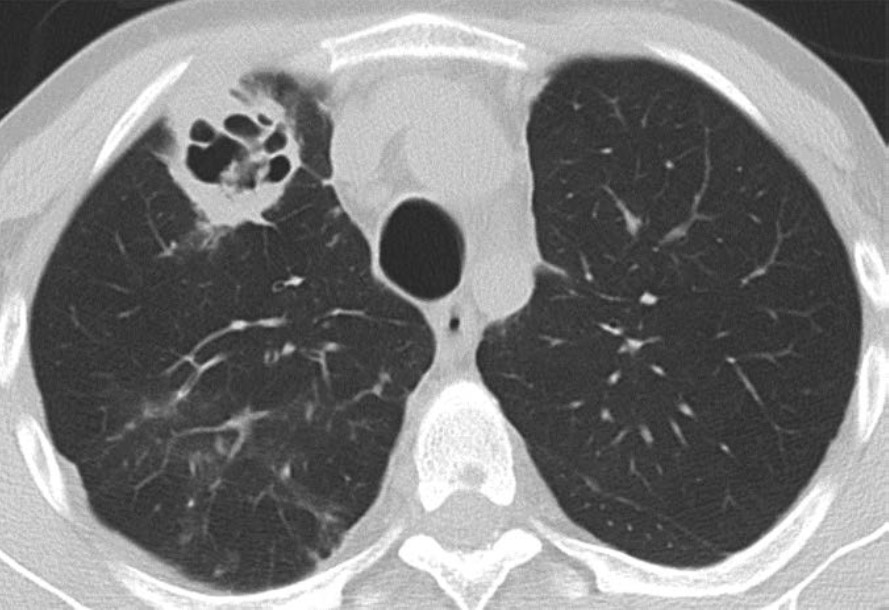

The clinical and imaging manifestations of pneumonia in transplant recipients are similar to those of nontransplant patients. Lung transplant recipients who present with dyspnea, cough, or fever are evaluated for pneumonia. Imaging findings of pneumonia include consolidation, ground-glass opacities, septal-line thickening, and pulmonary nodules. Pulmonary nodules can be single or multiple; they may be solid or ground-glass in attenuation. Cavitary nodules and nodules with ground-glass halos can occur, especially in patients with fungal pneumonia. Imaging studies should be scrutinized for complications of infection such as pulmonary abscess and bronchopleural fistula. Patients may also have reactive pleural effusions or reactive mediastinal or hilar lymphadenopathy. Treatment is the same as in nontransplant patients and consists of antibiotics, antivirals, or antifungals depending on the causative pathogen. Figure 4 shows three different lung transplant recipients with pneumonia.